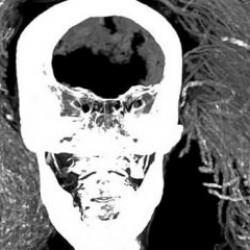

McDowell, 'Maria' olarak adlandırılan 'uzaylı' mumyanın parmak izlerinin bilinen hiçbir insan desenine uymadığını belirtti.

McDowell, "Bu parmak izlerinde döngüler veya kıvrımlar görmedik, Maria'nın parmak izleri insan izleriyle uyumlu değildi." dedi.

McDowell, mumya vücudunun büyük bir kısmının diyatomlu toprakla kaplı olduğunu ve parmaklarındaki epidermal sırtların çoğunlukla düz çizgiler halinde olduğunu belirtti.

Maria, Nazca bölgesinde bulunan ve 'Nazca mumyaları' olarak adlandırılan örneklerden sadece biri.

Bu mumyalar, uzun kafaları ve üç parmaklı elleriyle ünlü. Maussan ve ekibi, bu mumyalar üzerindeki bilimsel ilgiyi artırmak için yoğun çaba sarf ediyorlar. Ancak, Peru Kültür Bakanlığı gibi bazı kurumlar bu mumyaları insan yapımı sahte eserler olarak nitelendirdi.